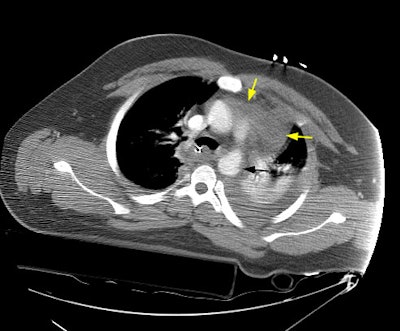

A CT scan of the chest demonstrated a large mediastinal hematoma (yellow arrows) and a left pleural fluid collection that was subsequently found to be a hemothorax. There was irregularity to the aortic arch near the isthmus (black arrow) which is highly suspicious for an aortic laceration, however, images at the level of the diaphragmatic hiatus demonstrated a more impressive finding (below).

CT images more inferiorly revealed an intimal flap and marked irregularity to the contour of the aorta consistent with traumatic injury (black arrows). Slightly below this level there was a near complete lack of opacification of the vessel (lower image).